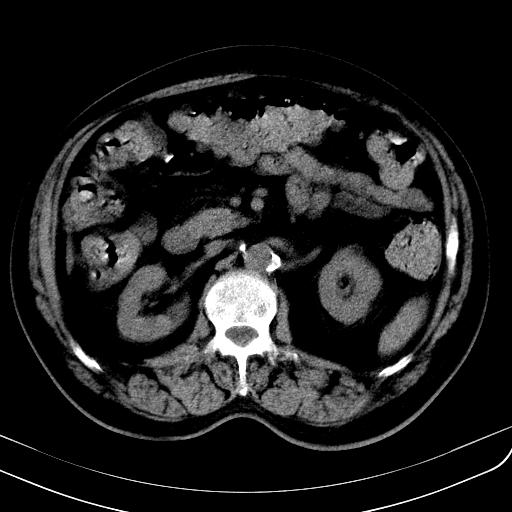

胃底靠近胃大弯处可见一圆形软组织影,直径为3.45cm,ct值约为30.1hu

间质瘤或神经鞘瘤。

考虑胃底平滑肌瘤。血肿不除外。